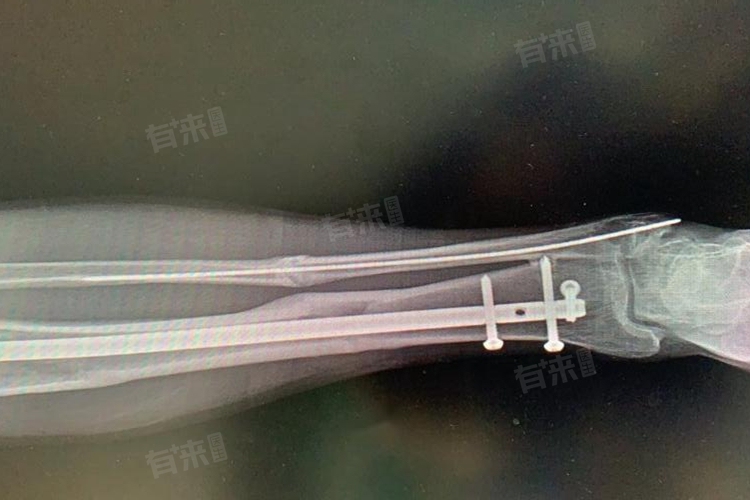

- 对于急性期,大约持续10到14天,在此期间,重点转向了保护并稳定骨折部位,确保断骨能够正确对齐,并维持这种位置直至愈合。根据骨折的具体情况,医生可能会采用石膏固定、夹板支持或是手术内固定等方式来实现这一目标。通过这些手段,不仅可以防止骨折端移位,还能够创造一个有利于新骨生长的环境。

3、监测恢复进展:定期复查以监控骨折愈合的情况非常重要,通过X光或其他影像学检查,医生可以评估骨头是否按照预期的方向正确愈合,并根据实际情况调整治疗方案。